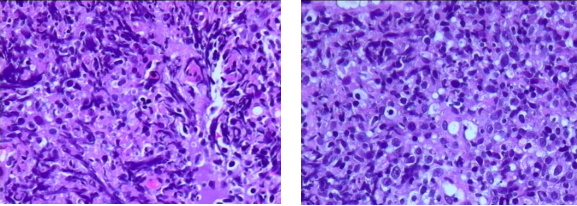

➤提示:(左侧鼻咽)非霍奇金淋巴瘤

,B细胞性,弥漫大B细胞淋巴瘤,GCB免疫表型亚群

图 1、患者病理学检查结果

➤鼻咽粘膜内见异型的淋巴细胞浸润,瘤细胞中等大,核不规则、染色质较细腻,核仁不明显,弥漫分布,部分细胞挤压变形。

➤免疫组化结果:CD20(+++),CD3(-),CD5(-),CD19(++),EBERs(-),Ki67(90%+),CD30(-),CD23(-),CD10(-),CD21(-),ALK(5A4)(-),Bcl6(60%+),CD138(-),MUM1(-),Bcl2(100%+),Cyclin D1(-),C-myc(70%+)。C-MYC BA FISH(-)